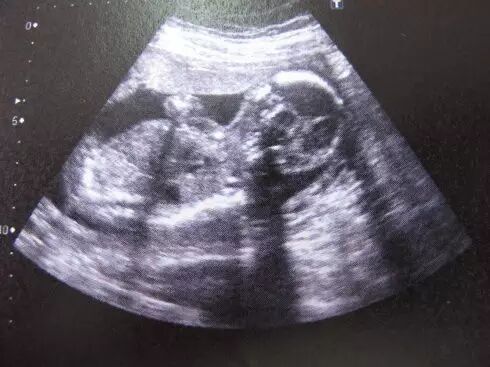

B超最早采用的是黑白超声诊断技术,通过发射超声波,使超声波遇到屏障产生回声,利用电脑收集这些回声,转化为相应的图像在屏幕上显示出来。通过超声探头测得的图像是黑白的,只能观测到胎儿的组织结构,测量头有多大、身有多长。

普通B超和彩色B超都是二维平面图像,这两种技术仍在使用,但由于观测效果较为依赖羊水量和胎儿体位,一旦在怀孕晚期羊水减少或者胎儿面向母亲的背部,观测效果就不太理想。

而且,二维图像不能满足准妈妈们"看到"宝宝模样的愿望。

三维彩超就是将二维图像合成模型,透过屏幕可从各个方位观察胎宝宝。